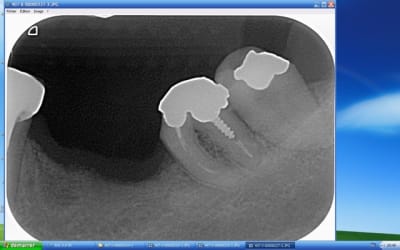

quelques rétroalvéolaires:

la 26 est morte: pas de mobilité mais lésion endo-paro distal irrécupérable. Si pose d'implant, faudra greffer le sinus avant.

En fait seule la 36 est très légèrement mobile.

la radio des dents 12-13 illustre parfaitement mes doutes:

Après avoir vu en conf Genon procéder à des chir paro (gingivectomie à biseau ext + plastie osseuse) sur les secteurs antérieurs, chez des bruxos pour gagner de la surface dentaire (en vue de faire les CCM par la suite) sans augmenter de façon inconsidérée la DV, je me disais que j'aurai pu proposer la même solution chez ce patient.

Oui mais..., c'était avant de faire la radio où on voit de petites racines et bien coniques par dessus tout... bref tout ce qui peut être défavorable et contre-indiqué cette solution... :-(